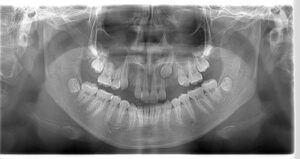

埋伏歯の診断方法

埋伏歯は外から見えないため、以下の検査が必要です。

-

パノラマレントゲン:全体の歯の位置を把握

CT撮影:位置・方向・深さを三次元で正確に確認

口腔内検査:歯の状態・骨隆起の有無を確認

特にCTは、牽引の難易度やリスクを判断するための重要な資料となります。